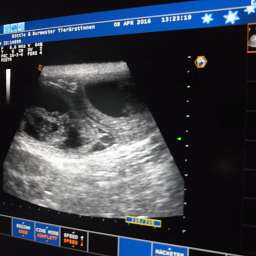

8.4.2016, 30.Tag: Heute ist ein großer Tag. Nicht nur für unsere kleine Mami Adele. Auch für uns und einige Menschen, die ihr kleines Wunder heiß ersehnen. Der Ultraschalltemin ist heute um 11.00Uhr. Hoffentlich hat Adele genug innere Ruhe und Ausgeglichenheit, um dem Stress adäquat begegnen zu können. Drückt bitte alle die Daumen. Unsicherheit scheint manchmal mein 2.Vorname zu sein...

18.00Uhr: Es ist vollbracht: "Lieber Nacho, wir dürfen Dir gratulieren. Du wirst Papa."

Mit pochendem Herzen durften wir 4 pochende Herzen unter Adeles pochendem Herzen sehen. Es ist immer wieder ein besonderer Moment. Das Wunder des Lebens nimmt seinen Lauf. Also, Ihr dürft Euch freuen: es sind mindestens 4 kleine Wunder unterwegs. Sucht Euch doch schon mal eins aus:

Adeles Gewicht aktuell 6,25Kilo.